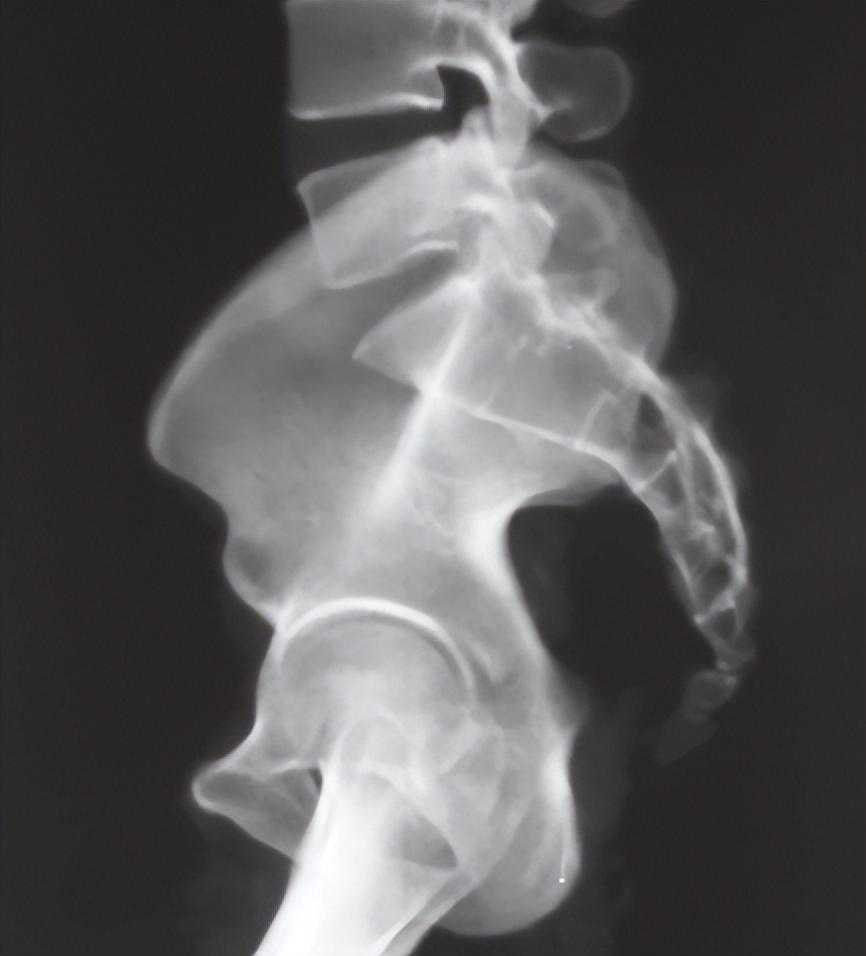

5、骨盆侧位X线检查:

即双侧坐骨大切迹完全重叠位,可见髂骨皮质密度线:显示骶髂关节髂骨部分前方皮质增厚部分,可以估计斜坡的位置(图6)。

图6骨盆侧位X线片